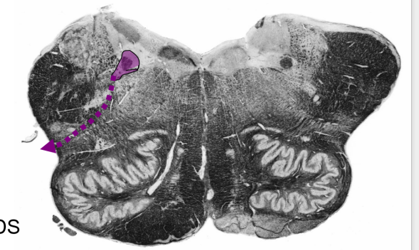

Describe Sensory Decussation of the Dorsal Columns:

Pathway? Locations?

What are the names of the fibers decussating?

Sensory Decussation of Dorsal Column

Dorsal Columns → ascend to caudal medulla → synapse @ gracile/cuneate nucleus

Location: deep to gracile tubercle (clava) and cuneate tubercle

dorsal column nuclei → Decussates @ tegmentum → medial lemniscus → ascend to thalamus (VPL).

Fibers Decussating = internal arcuate fibers

Fibers ascending in medial lemniscus = somatotopically organized